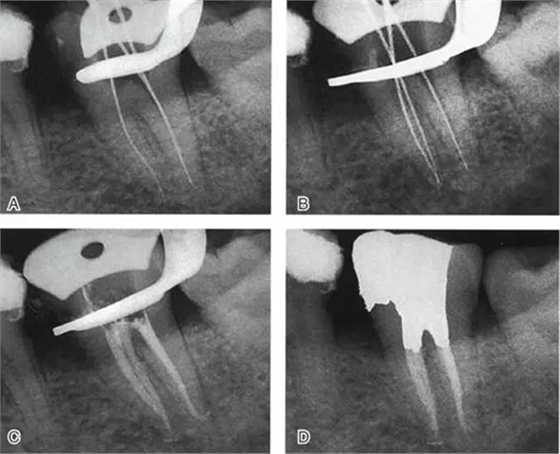

根管充填是C形根管治療成功與否的最重要因素。充填C形根管系統(tǒng)時(shí),近舌及遠(yuǎn)中根管可以進(jìn)行常規(guī)充填。關(guān)于狹區(qū)的充填,更適合以熱牙膠垂直加壓充填,這種方法可使牙膠到達(dá)根管系統(tǒng)的每一死角(圖4~7)。

圖6 Ⅱ型C形根管治療典型病例,A:初尖銼片,B:主尖銼片,C:根充片,D:術(shù)后片